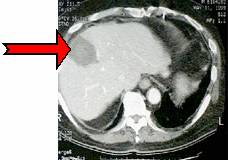

วิธีการนี้จะนิยมใช้ในการทำลายมะเร็งที่ตับ ทั้งแบบปฐมภูมิและแบบทุติยภูมิ โดยวิธีการนี้จะมีข้อดีกว่าการผ่าตัดแบบเดิมที่ใช้การเฉือนก้อนมะเร็งออกไปที่วิธีการนี้จะมีทำลายเนื้อเยื่อดีที่อยู่ในบริเวณใกล้เคียงในปริมาณที่น้อยมาก และถ้าเนื้อเยื่อบริเวณนั้นกลับมาเป็นมะเร็งอีกก็สามารถใช้วิธีการนี้ในการทำลายเนื้อเยื่อมะเร็งใหม่ซ้ำได้อีก นอกจากนี้ยังมีการสูญเสียเลือดที่น้อย มีรอยเปิดของแผลที่มีขนาดเล็กมาก ทำให้ใช้เวลาในการพักฟื้นสั้นไม่ต้องพักที่โรงพยาบาลนาน มีความเสี่ยงในการติดเชื้อที่น้อย มาก มีอัตราการกลับเป็นซ้ำของเนื้องอก (tumor recurrence rate) ที่ต่ำ (ประมาณ 1.8%7) และ อัตราการเกิดภาวะแทรกซ้อน (rate of complication) ที่ต่ำ (ประมาณ 3.6%) และเป็นภาวะแทรกซ้อนที่ไม่รุนแรง8 โดยอาการแทรกซ้อนนั้นได้แก่ การเป็นฝีที่ตับ (abscess) เลือดออก ปอดแฟบ (collapse of lung) หัวใจเต้นผิดจังหวะ และมีรอยไหม้ที่ผิวหนัง ภาพที่ 7 แสดงภาพเนื้อร้ายที่ตับก่อนและหลังจากใช้การรักษาด้วย RFA.

(ก) (ข)

ภาพที่ 7. เนื้อร้ายที่ตับก่อนและหลังจากใช้การรักษาด้วยคลื่นวิทยุ

(ก) เนื้อร้าย (tumor) ก่อนการรักษา

(ข) เนื้อร้ายที่ถูกทำลายด้วยคลื่นวิทยุ จะพบว่ามีขนาดใหญ่กว่าและสีเข้มกว่าเนื้อร้ายที่ยังไม่ถูกทำลาย แต่เมื่อเวลาผ่านไป ขนาดของเนื้อร้ายที่ตายแล้วนี้จะหดลงเพราะร่างกายจะดูดซึมและขับถ่ายเซลล์ที่ตายแล้วออกไป.9